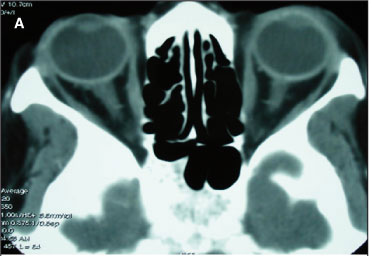

Devido ao aumento da escavação, à piora acentuada do defeito do CV, à perda de AV e à assimetria acentuada dos achados, a despeito do controle adequado da pressão ocular, foi considerado o diagnóstico de uma lesão compressiva do nervo óptico esquerdo e solicitada tomografia computadorizada (TC) de órbitas (Figura 2A) que se mostrou normal. A análise da TC realizada revelou, no entanto, que as regiões do nervo óptico intracraniano e do canal óptico não haviam sido estudadas adequadamente. Em decorrência disto, foi solicitada imagem por ressonância magnética (IRM) de alta resolução para estudar aquelas regiões. O exame revelou uma massa hipo-intensa em cortes enfatizando T1 com supressão de gordura e hiperintensa após injeção de agente paramagnético (gadolíneo), compatível com o diagnóstico de meningioma da bainha do nervo óptico acometendo a região do canal óptico e nervo óptico intracraniano (Figura 2B).